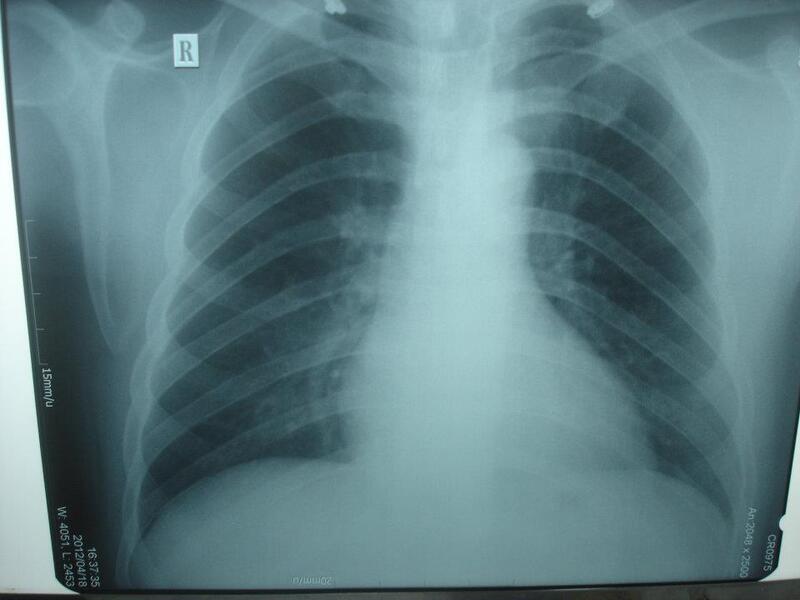

2. Chụp X quang phổi

Ở giai đoạn đầu của bệnh, chụp X quang có thể không phát hiện được bệnh do hình ảnh phổi bình thường. Khi bệnh phát triển đến giai đoạn nặng, chụp X quang phổi có giá trị gợi ý chuẩn đoán bệnh phổi tắc nghẽn mãn tính. Kết quả X quang giúp phân biệt biểu hiện ho, khạc đờm, khó thở là do bệnh phổi tắc nghẽn mãn tính hay các bệnh khác như lao phổi, giãn phế quản, u phổi, xơ phổi...